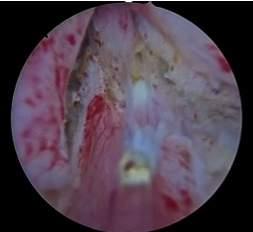

Figure 1.

18-F PSMA PET/CT in man with mixed prostate cancer (ductal plus acinar PCa Grade Group 4/Gleason score 8): intraprostatic standardized uptake value (SUVmax) was equal to 4 9 (a) in the absence of distant metastases (b)

Two Caucasian men 58 and 62 years old were admitted to our Department for dysuria: the patients had not familiarity for PCa and assumed antihypertensive drugs PSA values were equal to 5 6 and 2 8 ng/ml, digital rectal examination was highly suspicious for PCa and magnetic resonance image (mpMRI) showed for both the presence of a index lesion Prostate Imaging Reporting and Data System (PIRADS) score 5 The patients underwent extended transperineal prostate biopsy (18 cores) combined with four mpMRI/TRUS fusion biopsy using a 18 gauge needle under sedation and antibiotic prophylaxis (12, 13) The biopsy histology demonstrated the presence of a mixed PCa characterized by ductal and acinar PCa (Grade Group 4/Gleason score 8) with a Greatest Percentage of Cancer equal to 100%, a mean number of positive cores of 15 (3 targeted cores and 12 systematic biopsies)) and a mean total percentage of cancer equal to 45% (35-55%) The clinical staging performing lung and abdominal CT plus technetium-based bone scan did not demonstrate distant metastases and/or others primitive tumors; in addition, the 18-F PSMA PET/CT (5) showed in both patients an intraprostatic lesion provided of a standardized uptake value (SUVmax) equal to 4 6 and 4 9 in the absence of distant lesions suspicious for metastases (Figure 1) Following multidisciplinary evaluation, the patients underwent open radical prostatectomy (RP) plus extended pelvic lymphadenectomy Definitive specimen showed the presence in both cases of a mixed pT3bN1 PCa (ductal plus acinar Grade Group 4/Gleason score 8) with positive surgical margins, perineuronal invasion and nodes metastases (5/20 and 6/24, respectively) Postoperative PSA (one month from surgery) in the two patients was 0 8 and 0 3 ng/ml, therefore patients under-

Results: Conventional imaging was negative for distant metastases; 18F-PSMA PET/CT showed in both patients an intraprostatic lesion characterized by a standardized uptake value (SUVmax) equal to 4 6 and 4 9 in the absence of distant lesions suspicious for metastases Following multidisciplinary evaluation, the patients underwent radical prostatectomy plus extended pelvic lymphadenectomy Definitive specimen showed the presence in both cases of a mixed pT3bN1 PCa (ductal plus acinar pattern Grade Group 4) with positive surgical margins, neuronal invasion, and nodes metastases (5/20 and 6/24, respectively) Post-operative PSA in the two patients was 0 8 and 0 3 ng/ml, therefore patients underwent adjuvant therapy.